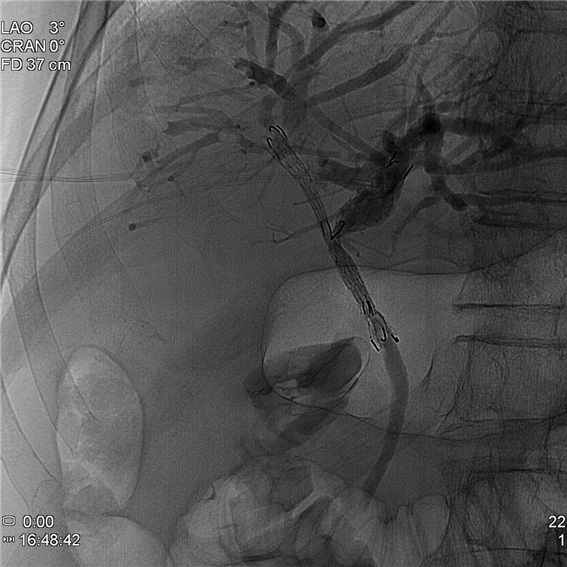

증례 3. 황달 증상으로 내원하여 간내 담도암 진단 환자에서 담도내시경을 이용한 금속 스텐트 시술 시행 2예